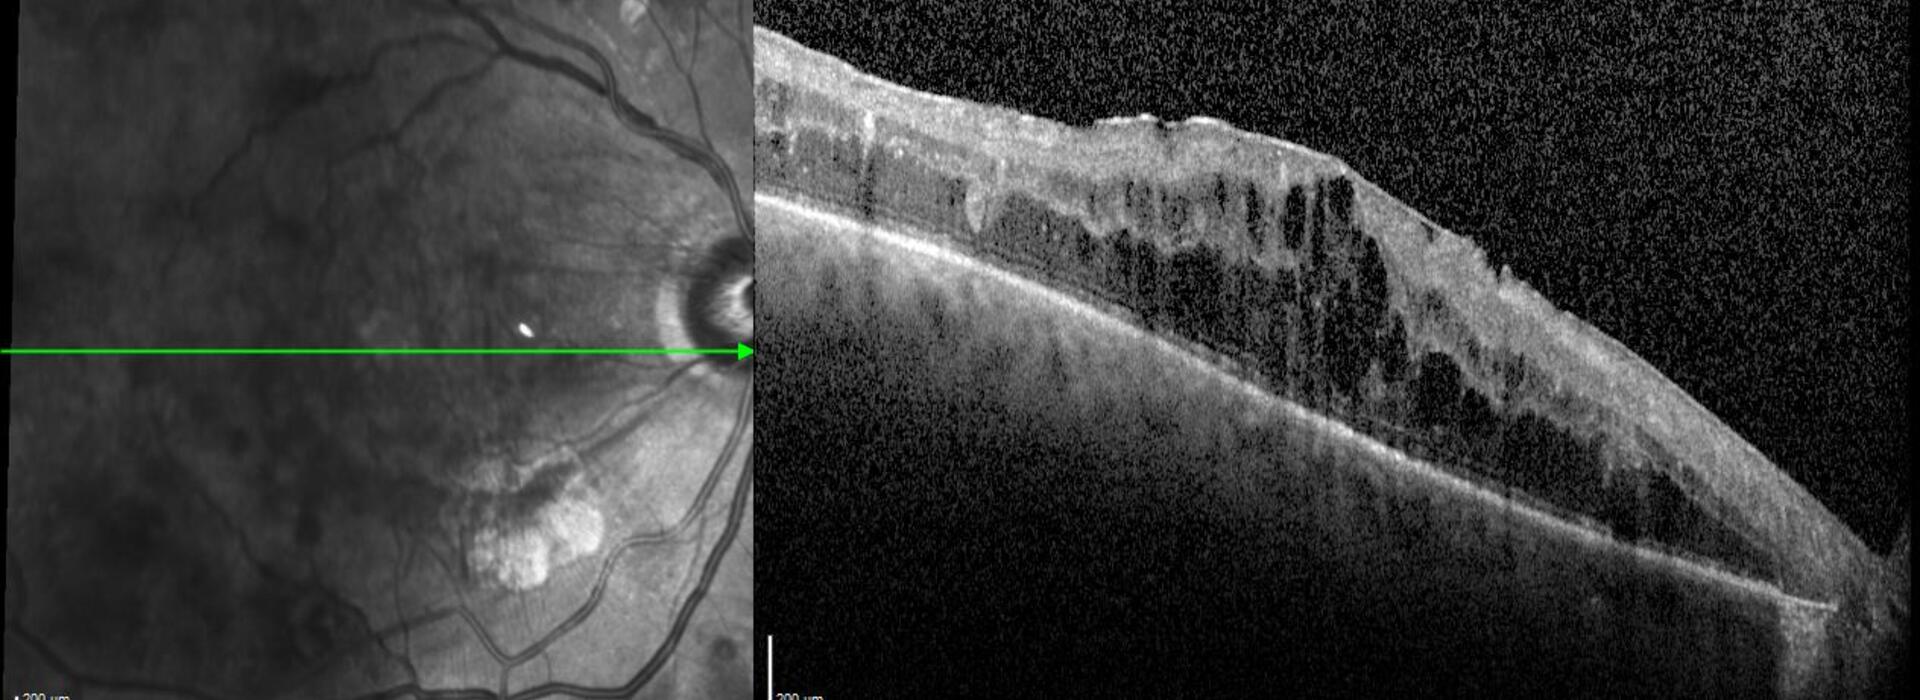

Clase 5 - Signos clave en diabetes ocular

OCT Summer Camp